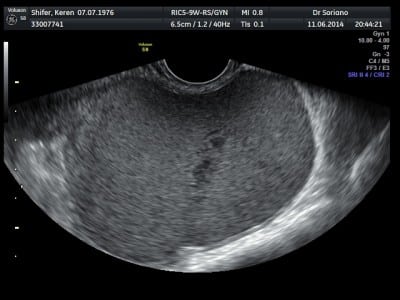

• בדיקת אולטרסאונד גינקולוגי

הופעת ציסטה שחלתית הינה מאורע שכיח, לעיתים כחלק ממחלת אנדומטריוזיס, אנדומטריומה, לעיתים בעקבות טיפולי פוריות, בד"כ מדובר בממצא שפיר. הטיפול בציסטה שחלתית עשויי להיות מעקב בלבד, גלולות או ניתוח לשם כריתת הציסטה בלפרוסקופיה ע"י מומחה על מנת להימנע מנזק לשחלה.

ציסטה בשחלה הינה מעין שק מלא בנוזל הממוקם בתוך השחלה, מהווה סיבה שכיחה לפניה למיון ולייעוץ גינקולוגי ועשויי לנבוע מסיבות שונות. הציסטות עשויית להופיע מסיבות שונות ומושפעות מגיל, טיפול בגלולות, צורת המחזור, מחלות רקע ועוד.

ציסטה היא מבנה במכיל נוזל מסוגים שונים, צלול, עכור, דמי, מכיל רק נוזל או חומר ג'לטיני ולעיתים מרכיבים מוצקים או הנמצא בתוך השחלה. כאשר ציסטה מופיעה בשחלה, היא מכונה ציסטה שחלתית. היא יכולה להתפתח כתוצאה משינויים הורמונליים, מחלות רקע כמו אנדומטריוזיס, גידולים בשחלה במרבית המקרים שפירים,  או בעקבות טיפולי פוריות. ציסטה שחלתית היא ממצא שכיח אצל נשים בגיל הפוריות ולעיתים אינה מצריכה טיפול. עם זאת, במקרים מסוימים הציסטה עשויה לדרוש התערבות רפואית, תרופתית או ניתוחית תלוי בגודל, מאפייניה  ותסמיניה.

האבחנה הראשונית נעשית במהלך הבדיקה הגינקולוגית ומישוש שחלה מוגדלת. בדיקת אולטראסאונד משלימה את הבדיקה. במקרים של ציסטה בשחלה מסוג ציסטה פוליקולרית ההמלצה להמתין לבדיקה חוזרת לאחר הווסת. על פי גילך יוחלט האם להמליץ על מתן גלולות למשך מחזור אחד או שניים והזמנה לבדיקה חוזרת.